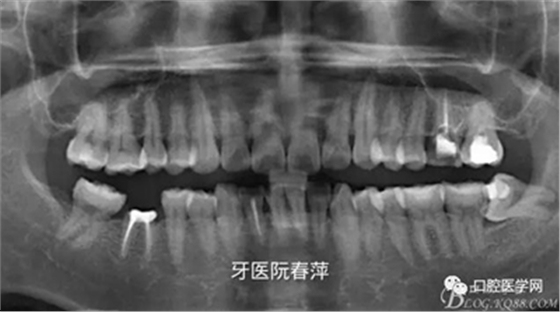

(5)X光片檢查:全景片看到25齲壞未近髓,26根管充填材料良好,27根管無充填材料,根尖區(qū)未見低密度影。

全景片如下圖

戴牙后全景片: